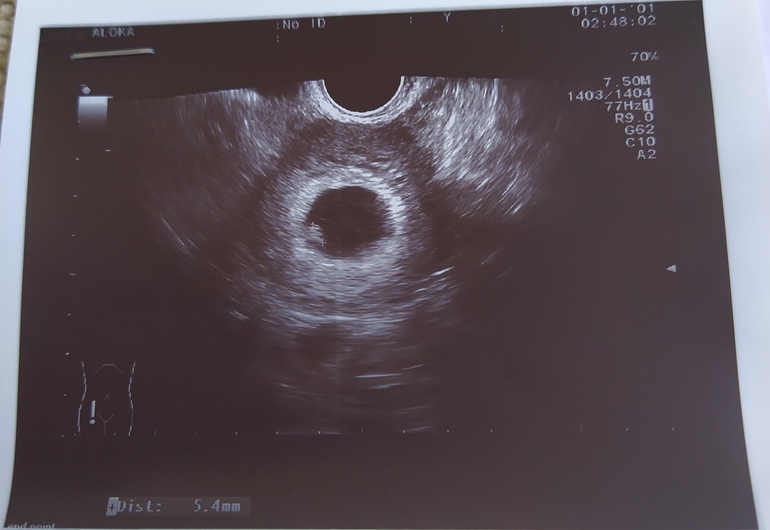

и у меня мальчик слева подтвердился-если узи вагинальное

Вот мой слева это мальчик у меня

У меня мальчик справа

если вагинальное узи то мальчик слева,если узи по животу то справа

У меня вагинальное узи в 5 недель сказали расположен справа , и оказался мальчик , сейчас тоже справа больше лежит